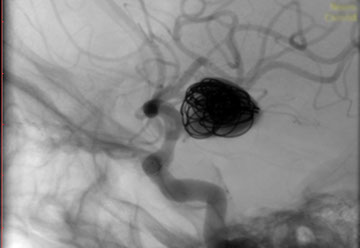

La paciente ingreso al Servicio de Hemodinamia el día martes 11 de febrero con un aneurisma cerebral gigante en la carótida izquierda y se le practicó una embolización; es decir una oclusión por dentro del mismo, donde se colocó un dispositivo denominado coils más un stent diversor de flujo. El procedimiento fue exitoso y contó con la colaboración de médicos neurointervencionistas del Instituto Oulton de la Ciudad de Córdoba.